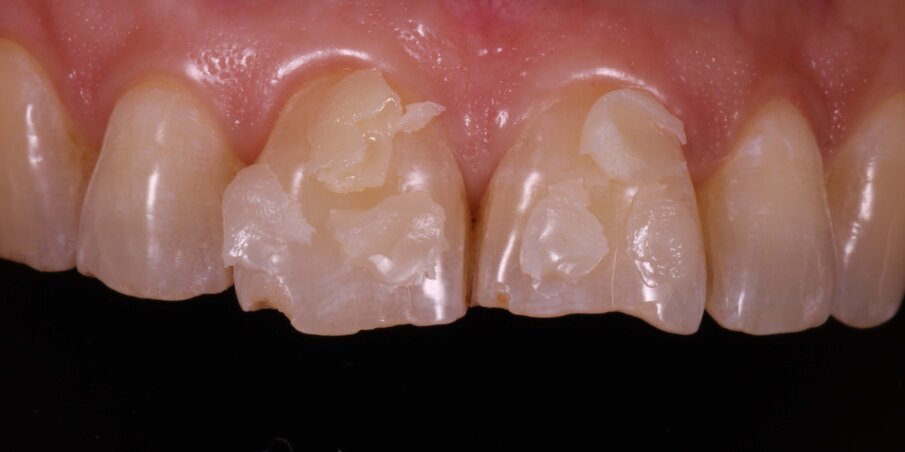

Intraoral examination and history: Trauma leading to fracture of the incisal edges of 11, 21 and 12 (Fig 5).

Fig 5: Pre op showing fractured incisal edges